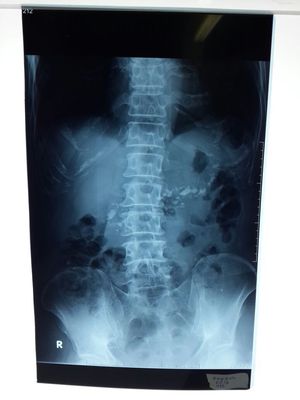

Scoliosis

Pneumoperitoneum???